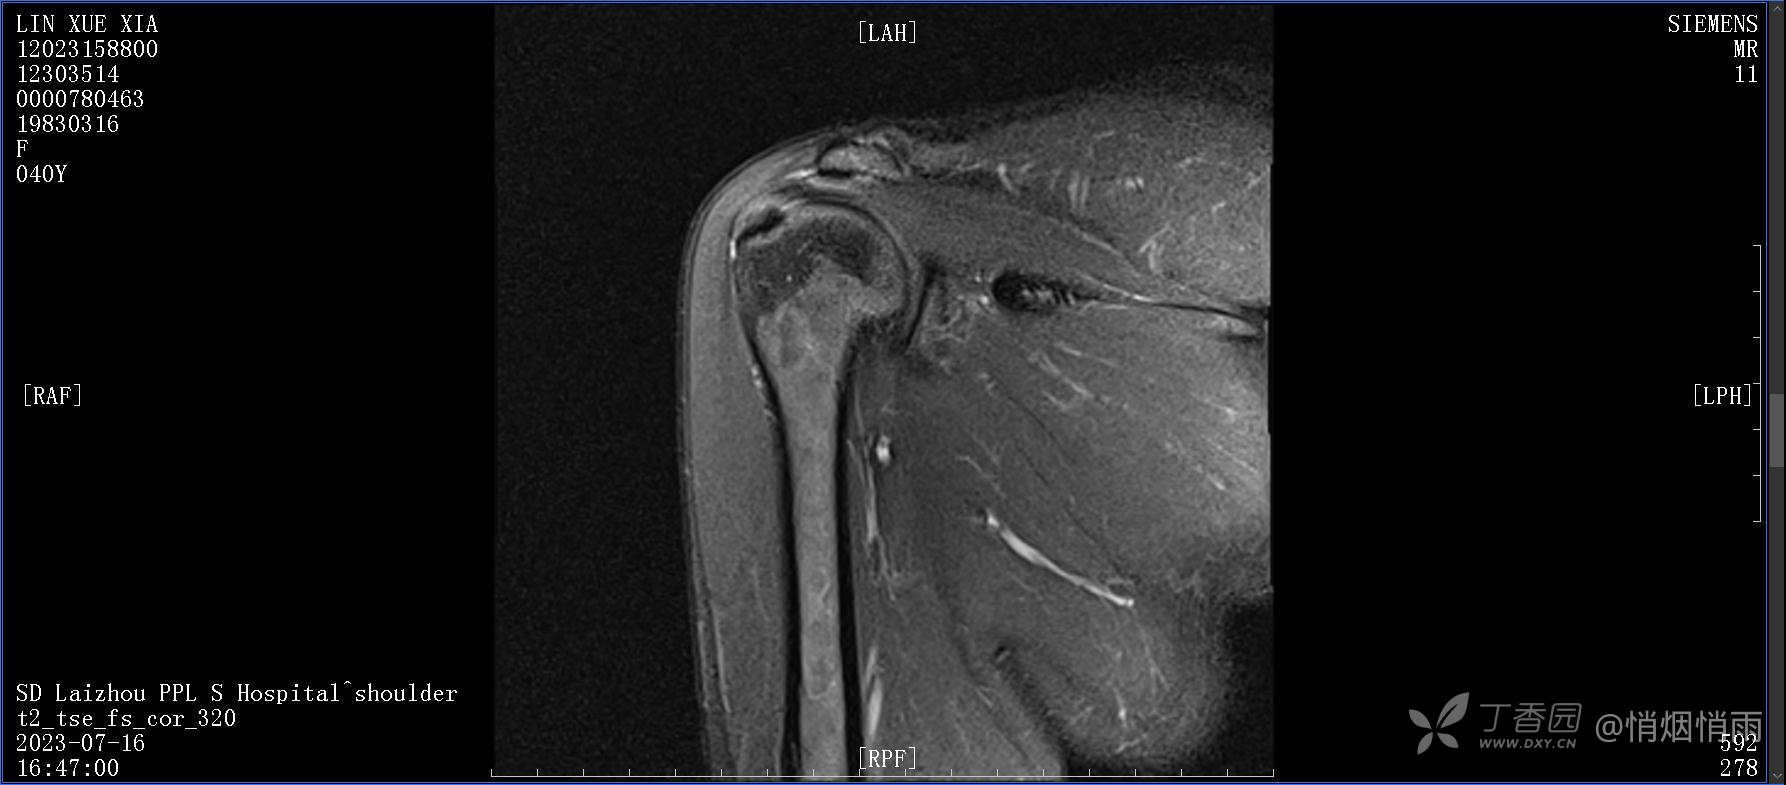

查体:右肩关节局部轻度肿胀,肩胛区压痛明显,痛处不固定,肩关节痛性活动受限,jobe test(+),lift -off test(+),中指、环指感觉较余指减退,余肢端感觉及血运情况可。

目前的诊断,暂时依据辅助检查诊为肩袖损伤,但是患者疼痛的性质和特点,却不是单纯的肩袖损伤所致。考虑过胸廓出口综合征,但是该疾病会出现肩胛区的疼痛吗?(由于考虑到费用的问题,没再进行下一步的检查)带状疱疹会有如此的症状吗?